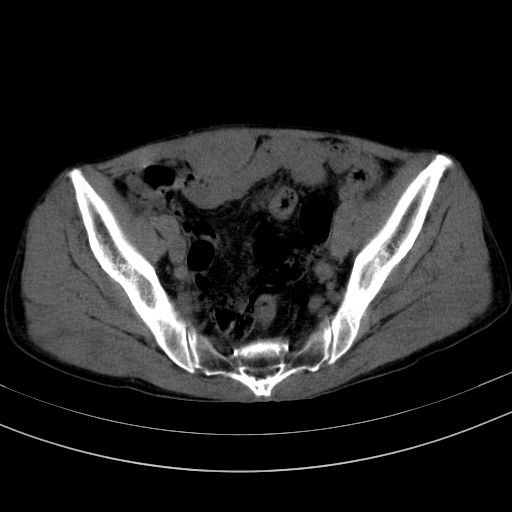

以下是引用37度在2010-1-9 14:37:00的发言:[br]1.双肾囊肿,左肾积水结石,.胆总管轻度扩张;[br]2.病灶在腹膜外,考虑纤维瘤。

以下是引用dyqct在2010-1-9 17:56:00的发言:[br]考虑:1.双肾囊肿,左肾积水结石、旋转不良。[br] 2.右侧腹直肌血肿或纤维瘤。[br]肠道准备不好。做个增强。